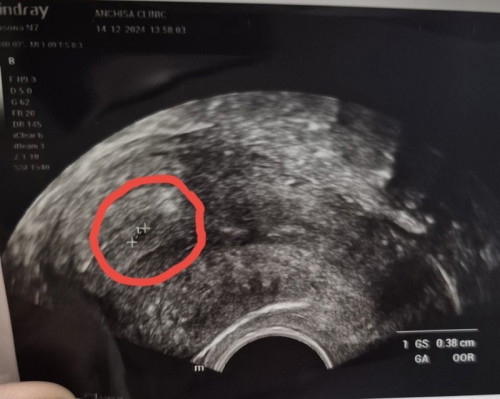

ขอสอบถามหน่อยนะคะวันนี้ลองไปซาวน์ดูครั้งแรก ถ้านับตามประจำเดือนน่าจะตั้งครรภ์ได้ 5 สัปดาห์ 6วัน หมอบอกว่าที่เป็นเครื่องหมายวงไว้น่าจะเป็นถุงตั้งครรภ์ แต่เล็กมากน่าจะไข่ตกช้าคำนวณจากประจำเดือนครั้งสุดท้ายไม่ได้ ในรูปนี่น่าจะเป็นถุงต้งครรภ์มั๊ยคะ ขนาดถุงประมาณ 3.8มมค่ะแต่มันจะรีๆ